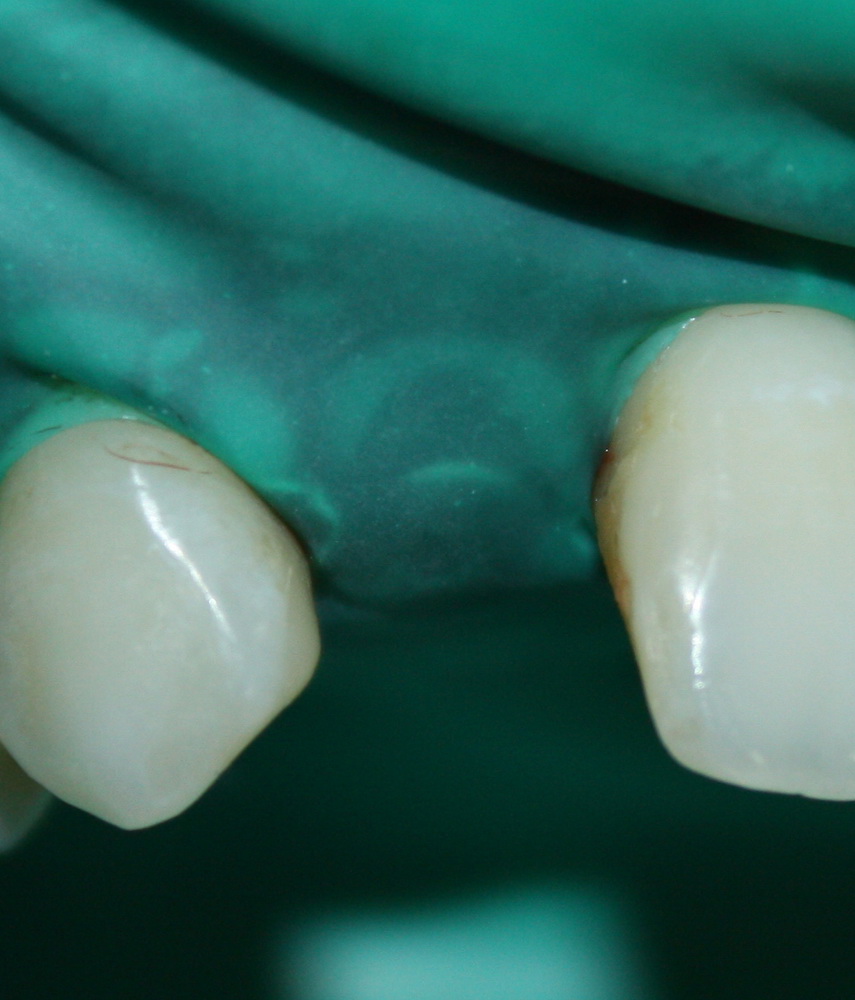

Поэтому мы с Давидом придумали следующее. Мы не стали удалять все зубы, оставили четыре клыка. Это самые большие зубы нашего организма, способные выдерживать значительную нагрузку. Эти четыре клыка Давид использовал как опору временного несъемного (!) протеза, состоящего из восьми (!) единиц на каждой челюсти:

на фотографии вы видите состояние этого протеза, примерно через полгода после начала лечения.